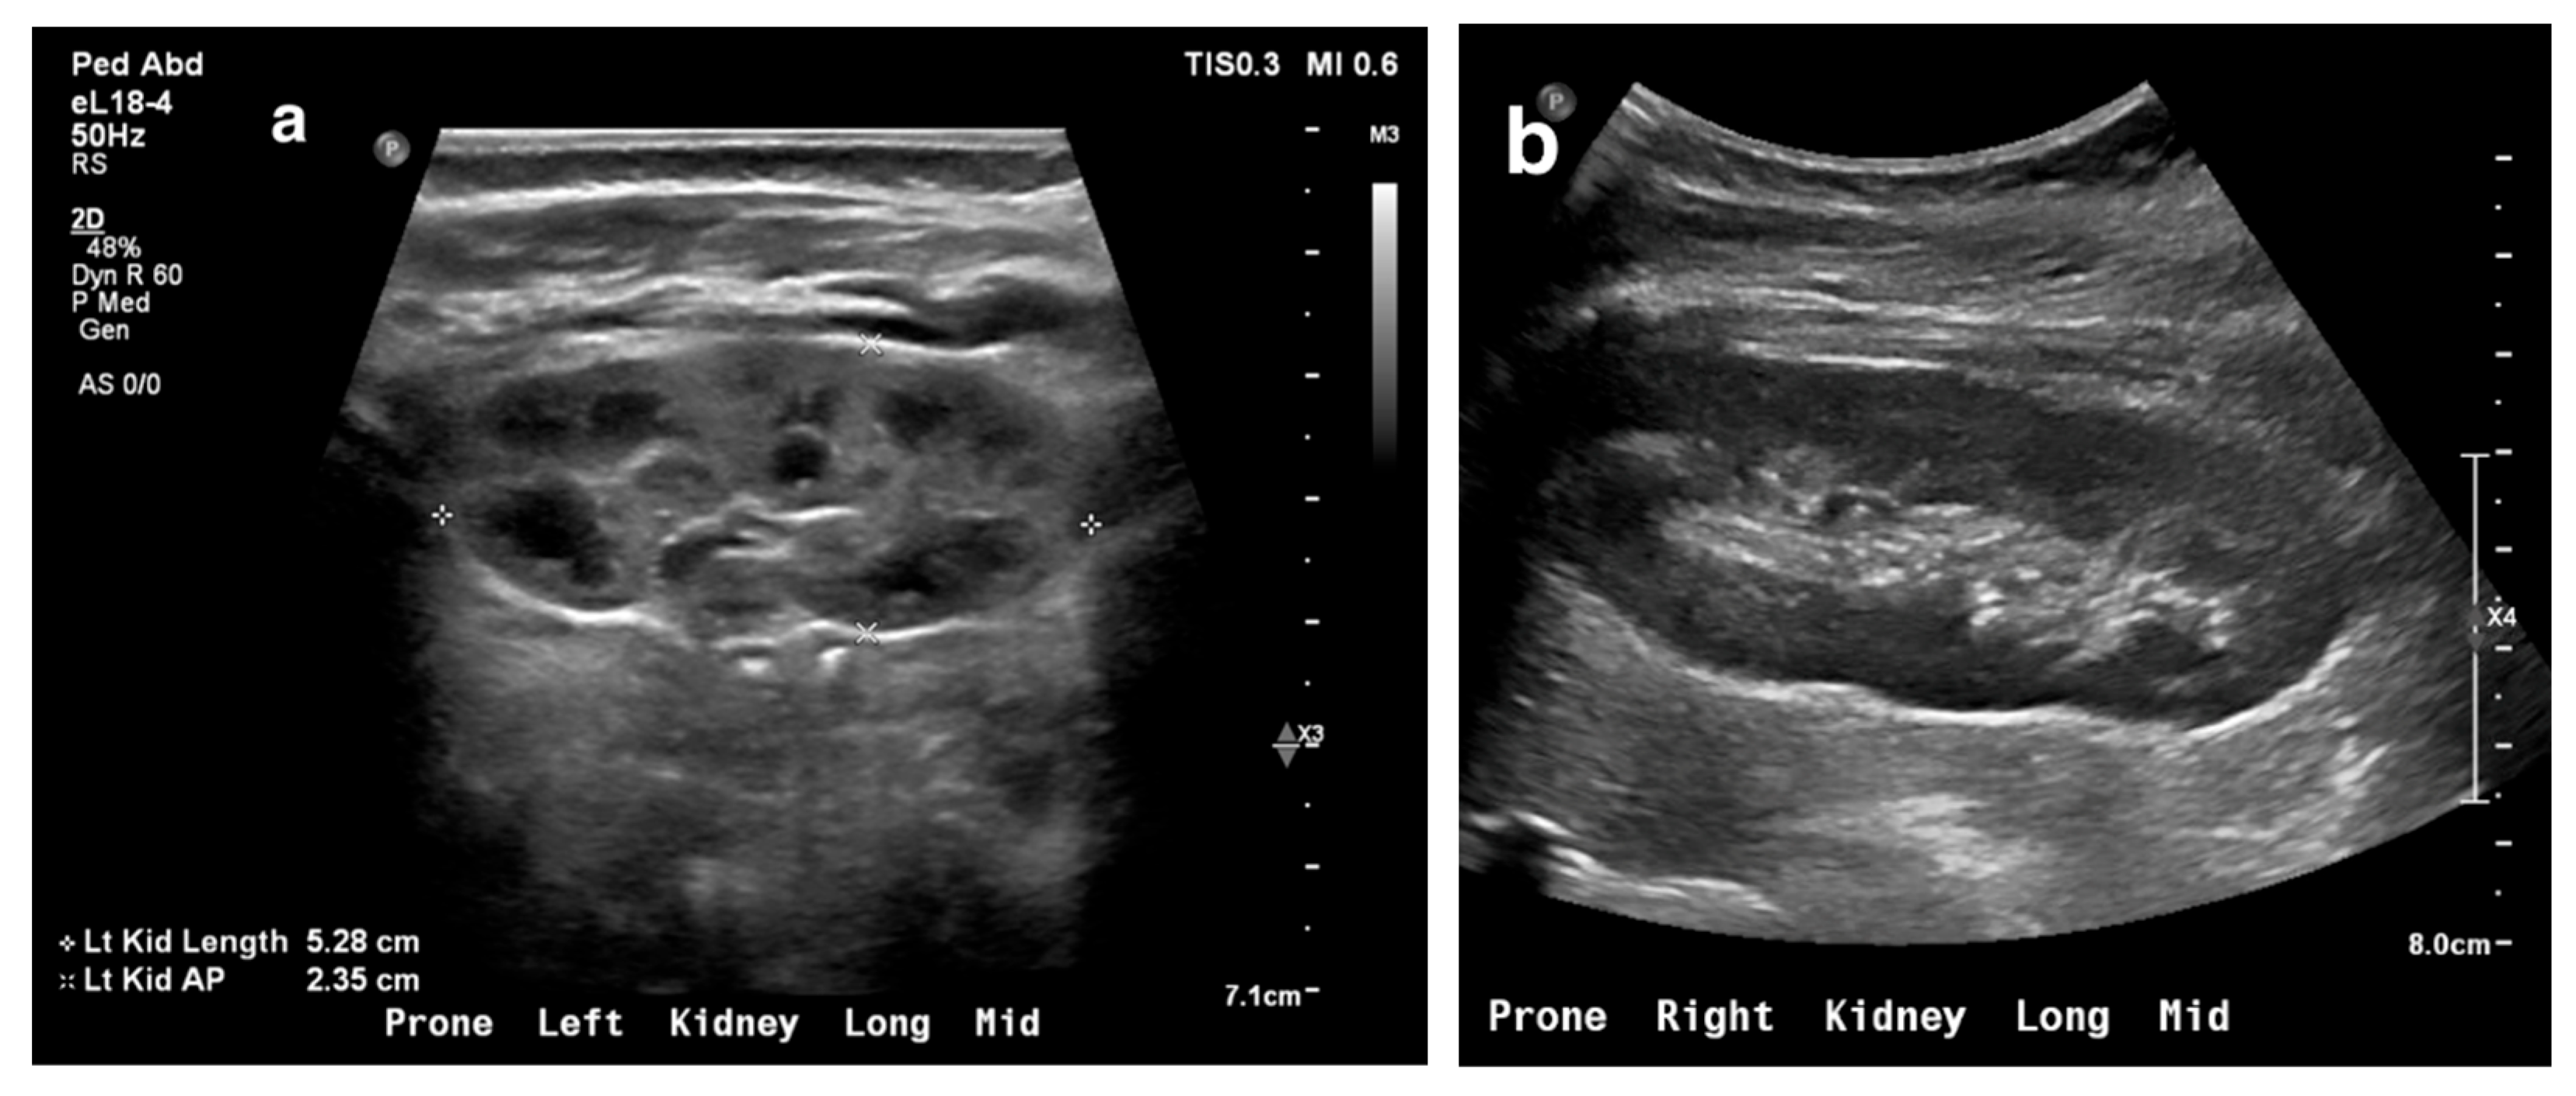

13. Obstructive Uropathy